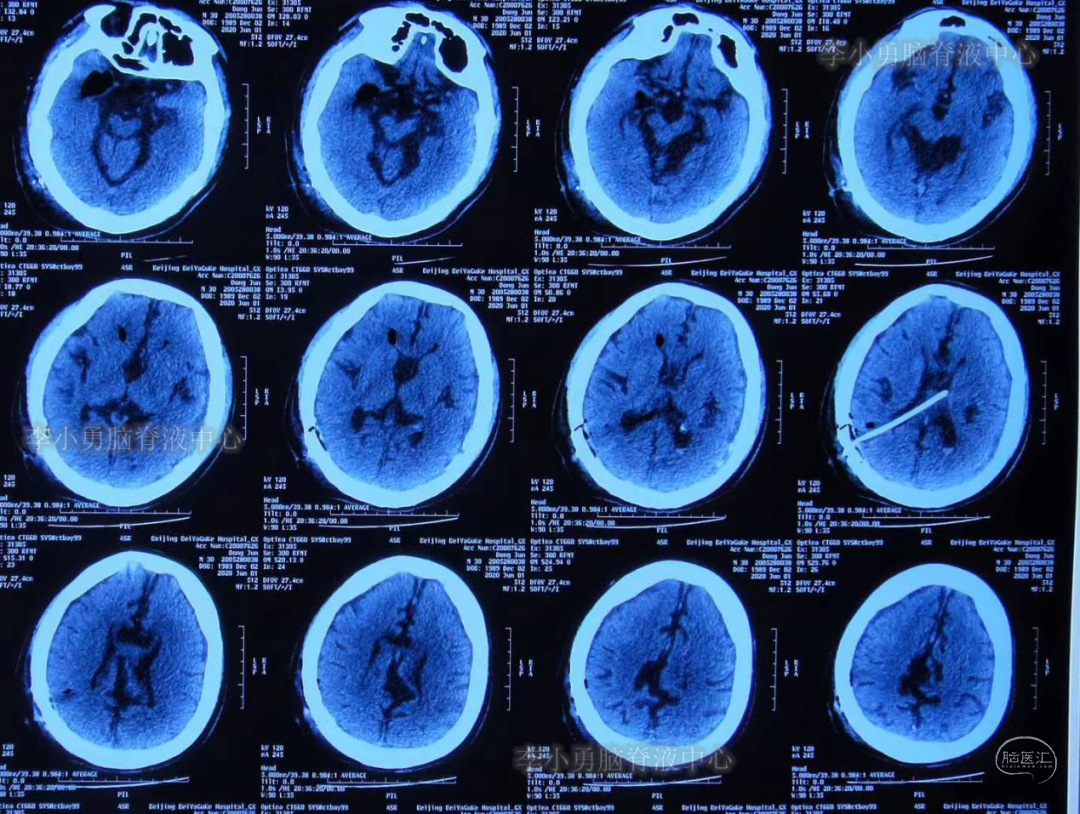

2020年5月28日入院时:扶入病房,表情痛苦,脾气暴躁,仍头痛头晕(图-3),入院当天查头部CT检查:脑积水分流术后状态(图-4)。

图-4:2020年5月28日头CT脑室腹腔分流术后状态

脑室外引流术后第3天即2020年6月4日,复查头部CT(图-7)见脑室系统较前缩小。

图-7:2020年6月4日头CT脑室系统较前缩小

脑室外引流术后第23天即2020年6月24日,复查头部CT见脑室系统较前无明显变化(图-10),但从2020年6月5日-2020年6月24日18天内仅出现过3次头痛(注:术后5天时曾每2-3天头痛发作一次),且头痛程度较前明显减轻。

图-10:2020年6月24日头CT